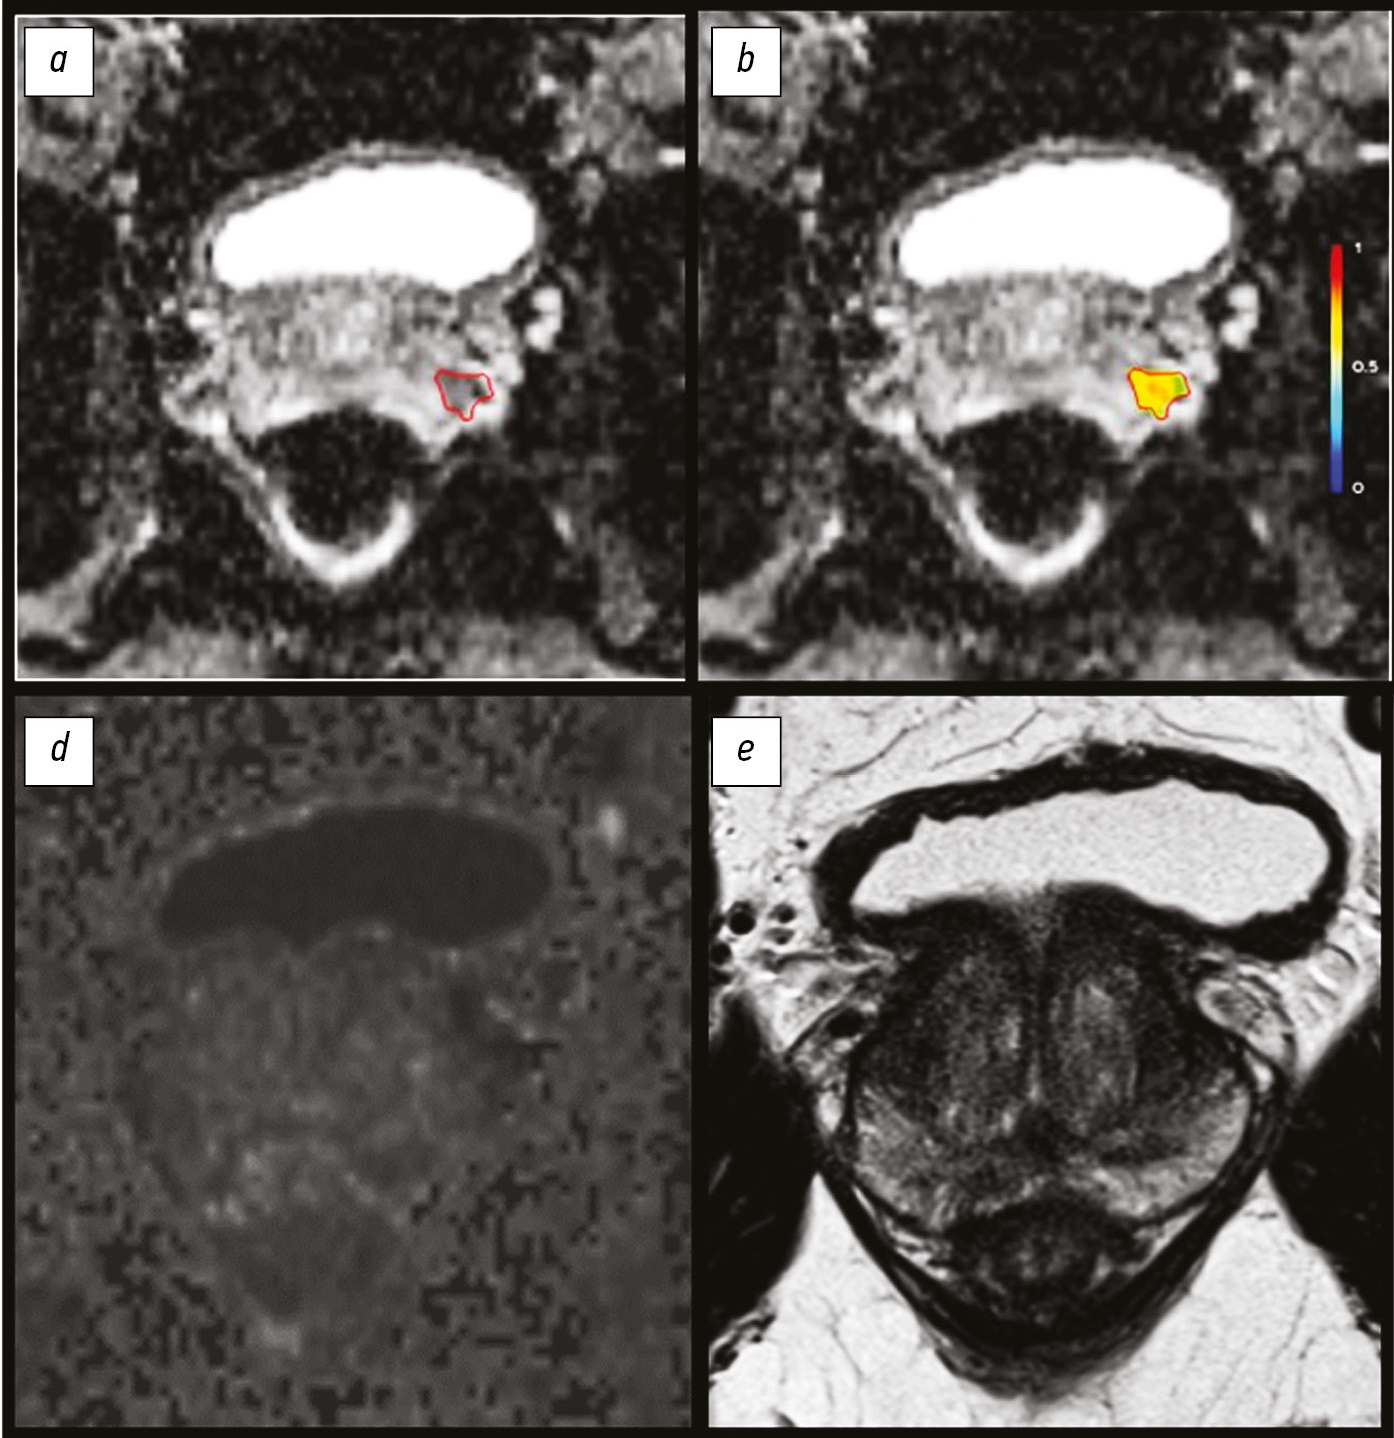

This study presents a rare clinical case of encapsulated necrotic pancreatitis, which was a complication of acute pancreatitis that arose against the background of alimentary disorders. The aspects of the semiotics of radiation diagnostic methods in the follow-up control of these pathologies were presented.

This case is notable for the manifestation of diseases upon hospital admission, as in the classical edematous form of acute pancreatitis, with a further increase in negative dynamics. This demonstrated the possible stepwise disease development, accompanied by a series of follow-up computed tomography between the clinical and morphological phases of acute pancreatitis and before the formation of pancreatic necrosis, which was complicated by sequestration of the pancreatic body with peripancreatic abscess formation. Afterward, the therapeutic paradigm was changed, and the place of the conservative approach was taken by active surgical tactics, followed by repeated manipulations and follow-up computed tomography and magnetic resonance until the improvement of the patient’s condition.

471-480